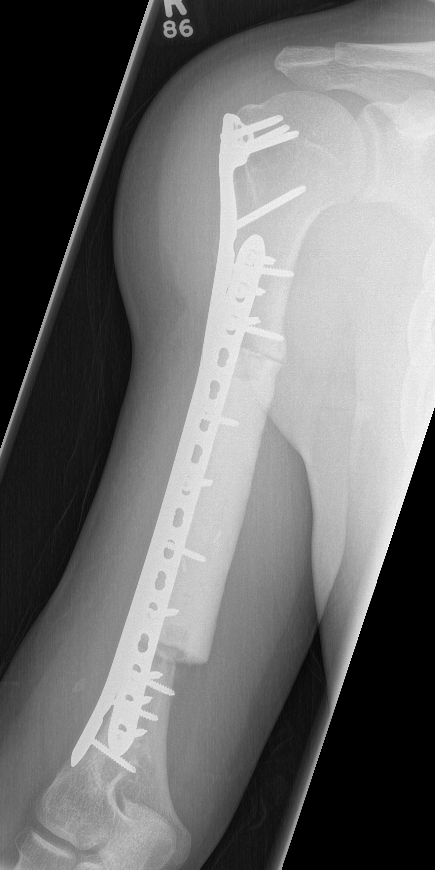

High grade / Wide resection

Wide resection